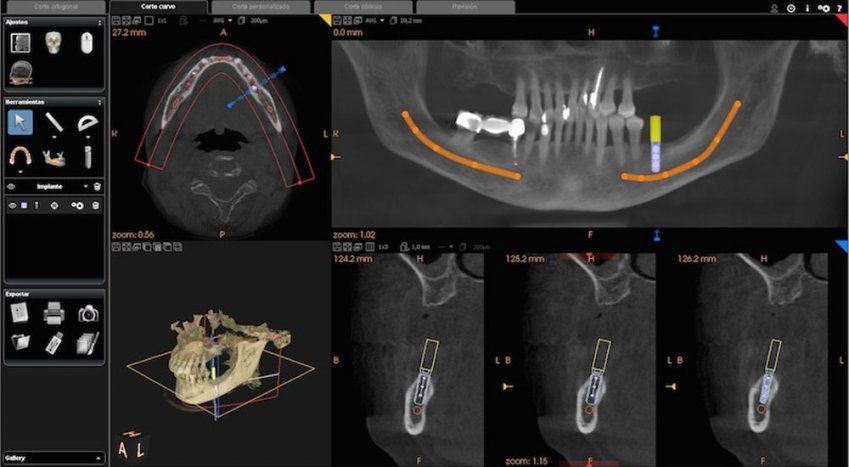

En el centro de Radiologia Maxilo Facial Dr. Mayor nos hemos mantenido a la vanguardia en el sector y por eso somos uno de los centros de referencia a nivel nacional en la realización de estudios maxilofaciales. Además, podemos decir que somos uno de los primeros centros que incorporó la tecnología 3D a sus instalaciones, lo que nos permite hacer estudios muy avanzados y completos, como los TAC dentales (Dentascan, Cone Beam CT) dirigidos a todo tipo de pacientes.

En los centros de Imagen Diagnóstica Dental Dr. Mayor ofrecemos una amplia variedad de servicios, gracias a la moderna aparatología con las que contamos.

Las pruebas diagnósticas que realizamos en nuestro centro son las siguientes: